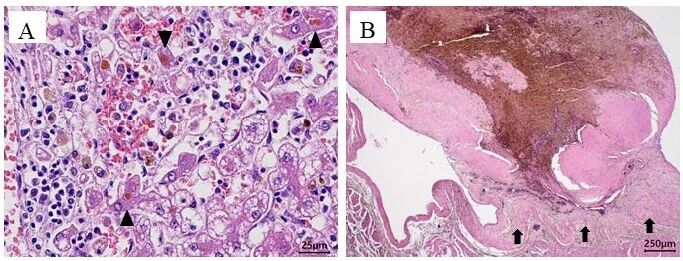

尸检和组织病理学检查结果包括梗阻性黄疸慢性肝炎和PVT(上图BC及下图)。

↑ 组织病理学发现。(A)肝脏:可见肝细胞慢性肝炎伴胆汁淤积(黑色三角),肝细胞的空泡变性,以及单核细胞浸润。(B)门静脉血栓形成:血栓主要由纤维蛋白、纤维化和色素组成,并与血管壁表现为纤维性黏连(黑色箭头)。